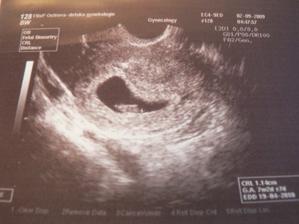

2.9.09 první fotečka našeho piškotka jsme 7 tt